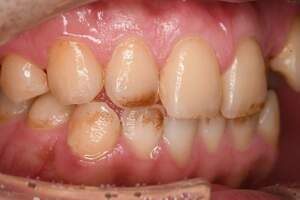

スケーリング

治療前

治療後

| 年齢 | 45歳・男性 |

|---|---|

| 主訴 | 歯石をとりたい |

| 治療内容 | 全顎歯石除去 |

| 治療期間 | 60分 |

| 費用 | 約2,000円(保険適用) (2022年7月現在) |

| 治療方針 | 約4年ぶりの歯科医院で歯のクリーニングを行いたいと来院されました。 歯石除去と歯の表面に付着したプラークを取り除きました。また、ご自身でしっかり歯磨きができるように、歯ブラシのレッスンも行いました。 |

| 担当者所見 | 歯石がなくなった変化に驚き、すっきりしたと喜んでくださいました。歯周病の進行がみられるので次回以降歯周病治療を行っていきます。 |